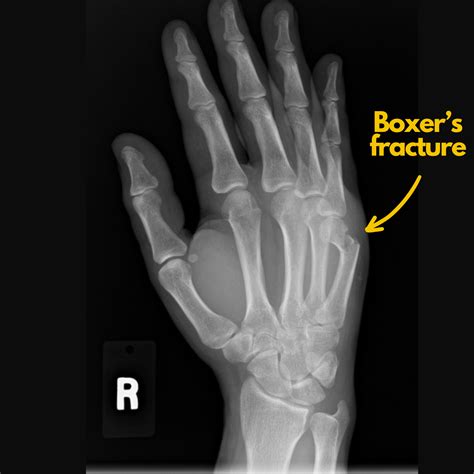

TitleWhat Is A Boxer’s Fracture? Does My Broken Hand Need Surgery — Dr. Nick Golinvaux